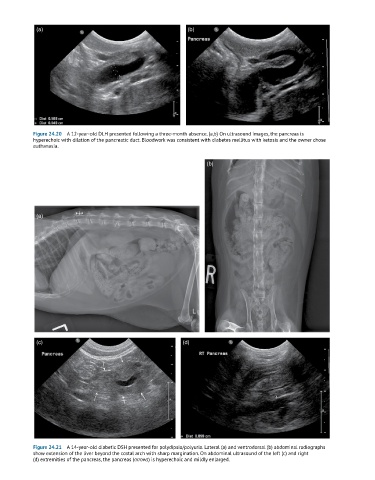

Figure 24.20 A 12-year-old DLH presented following a three-month absence. (a,b) On ultrasound images, the pancreas is

hyperechoic with dilation of the pancreatic duct. Bloodwork was consistent with diabetes mellitus with ketosis and the owner chose

euthanasia.

Figure 24.21 A 14-year-old diabetic DSH presented for polydipsia/polyuria. Lateral (a) and ventrodorsal (b) abdominal radiographs

show extension of the liver beyond the costal arch with sharp margination. On abdominal ultrasound of the left (c) and right

(d) extremities of the pancreas, the pancreas (arrows) is hyperechoic and mildly enlarged.